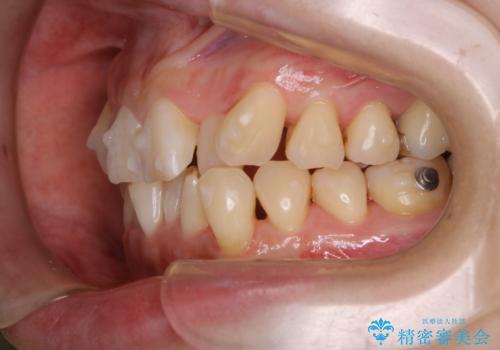

- インビザラインでのマウスピース矯正中に、歯の黄ばみが気になるため綺麗に白くしたいとのことでした。PMTC60分コースを行いました。

PMTC(保険外治療)は、毎日の歯磨きで落としきれない汚れや、コーヒ、紅茶・タバコのヤニなどの着色も除去します。目には見えない歯と歯の間・歯肉の境目・インビザライン中はアタッチメント周囲などに残っているプラーク(歯垢)もしっかり取り除きます。PMTCでは専門的な機械や材料を使用して、徹底的に汚れを除去するため、虫歯・歯周病・口臭予防などにつながります。